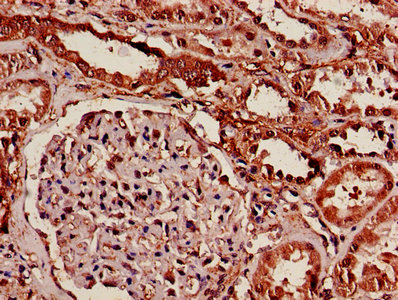

IHC image of CSB-PA01544A0Rb diluted at 1:600 and staining in paraffin-embedded human kidney tissue performed on a Leica BondTM system. After dewaxing and hydration, antigen retrieval was mediated by high pressure in a citrate buffer (pH 6.0). Section was blocked with 10% normal goat serum 30min at RT. Then primary antibody (1% BSA) was incubated at 4°C overnight. The primary is detected by a biotinylated secondary antibody and visualized using an HRP conjugated SP system.